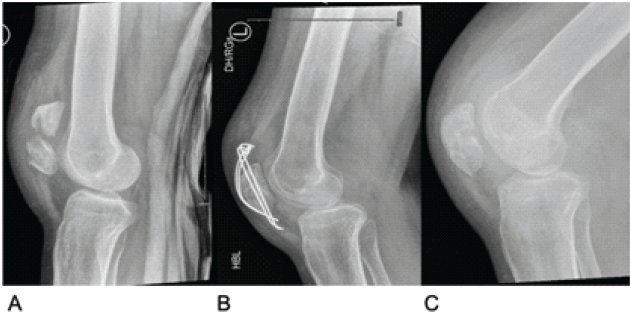

A man in his 20s who immigrated to Ireland from India reported non-specific knee pain. He had no significant medical history, and the episode was diagnosed as a soft-tissue injury, for treatment with non-steroidal anti-inflammatory medication. He presented to the Emergency Department 1 year later after a fall and hyperextension injury to his left knee. A displaced transverse fracture of the patella was confirmed on X-ray imaging. The initial laboratory investigations were normal, including an erythrocyte sedimentation rate (ESR) of 10 mm/h, a white blood cell count of 10.9 × 109/L, and a C-reactive protein (CRP) of 3 mg/L. The patient underwent open reduction and internal fixation using tension band wiring 4 days after the injury, and the surgery was uncomplicated. However, outpatient recovery was slower than anticipated, with persistent knee swelling. Range of motion remained limited to an arc of 10–90° despite adequate physiotherapy and rehabilitation. Given these issues, a decision was made to remove the implants 12 months after the initial surgery. All implants were removed without complications, and there were no abnormal findings intraoperatively. Upon re-evaluation in the outpatient department, the patient exhibited persistent knee swelling but no tenderness. Knee flexion to 110° was possible, and although quadriceps muscle wasting was noted, he managed to perform a straight leg raise (SLR). X-rays showed a healing patellar fracture without articular surface involvement, as shown in Fig. 1. He was discharged for ongoing community physiotherapy.

Figure 1: Lateral X-ray images of the left knee. (a) Initial fracture. (b) Tension band wiring. (c) After the removal of metal.